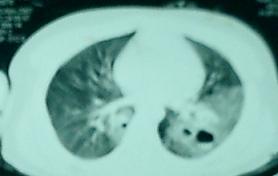

病人,男性,17岁,因车祸被120送到医院,做双髋ct示右髋臼粉碎性骨折,另做胸部ct偶然发现两肺多发空洞,向病人询问病史,既往无咳嗽/咳痰及胸痛.亦无午后低热及盗汗.后住院期间查血常规示白细胞和中性粒细胞比例增高

病人,男性,17岁,因车祸被120送到医院,既往无咳嗽/咳痰及胸痛.亦无午后低热及盗汗.后住院期间查血常规示白细胞和中性粒细胞比例增高

先考虑:双肺挫伤、肺撕裂伤伴气瘤形成可能性大。

双下肺以肉芽肿增殖形式为主伴发空洞,且患者无临床症状,应首先考虑霉菌性肺炎伴空洞形成但结核不能除外

双肺下野但斑片状影,内有梭形低密度影,结合外伤史考虑肺挫裂伤-假囊肿形成。[emb14]

厚壁空洞,空洞内见软组织影,考虑曲霉菌感染?